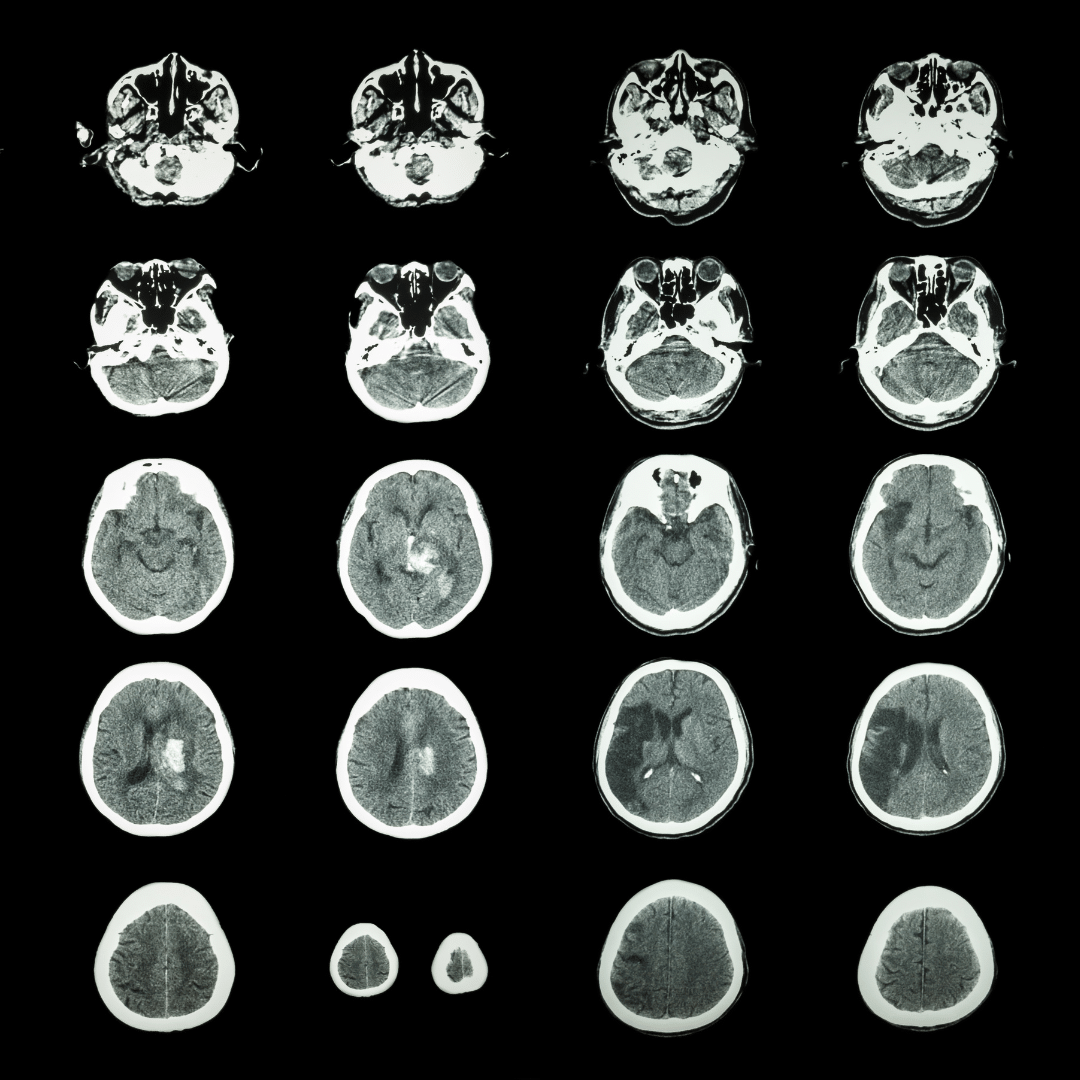

Usually an SCI is discovered when a patient receives a brain scan for some other reason, or if the patient is experiencing otherwise unexplained mild symptoms that mimic stroke damage. A silent stroke will appear on the patient’s brain scan as white spots or scar tissue, or if recent, swelling, inflammation, or bleeding.